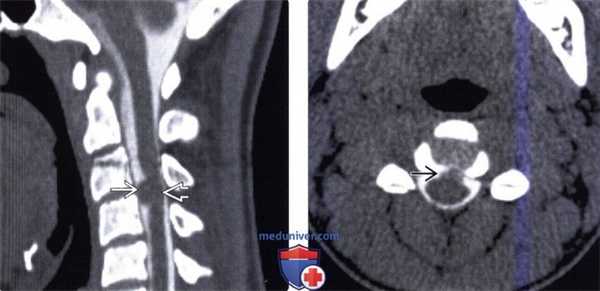

3. КТ признаки нейроэнтеральной кисты:

• КТ с КУ:

о Гиподенсная внутриканальная киста, минимально либо вообще не накапливающая контраст

• Костная КТ:

о Фокальное расширение спинномозгового канала, увеличение межпедикулярного интервала

о Аномалии развития позвонков «50%, обычно у пациентов детского возраста): расщелины позвонков, «позвонки-бабочки», аномалии сегментации

(Слева) На сагиттальном КТ-срезе после введения контраста определяется вентральное интрадуральное объемное образование В на уровне СЗ-С4, умеренно сдавливающее спинной мозг.

(Справа) На аксиальном КТ-срезе после интратекального введения контраста определяется вентральное интрадуральное объемное образование, представляющее собой нейроэнтеральную кисту. Признаков аномалий сегментации позвонков не видно.